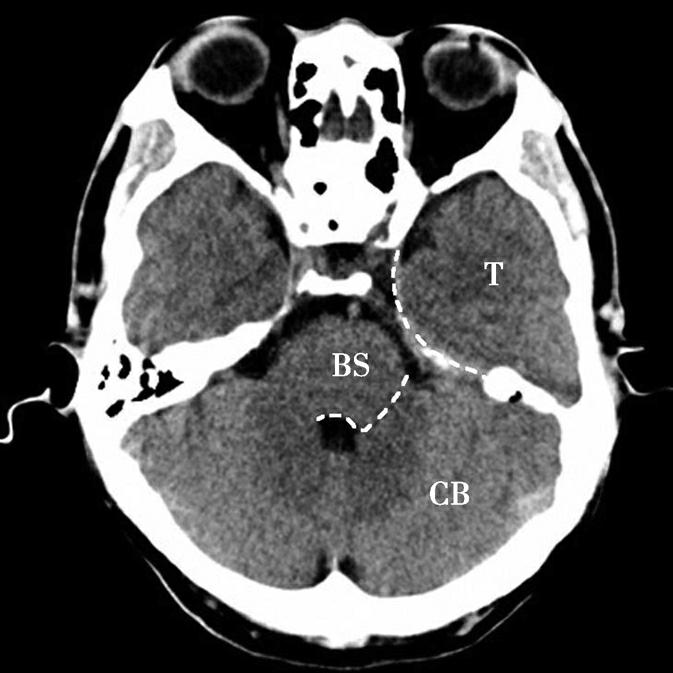

重要结构:脑桥小脑角池、脑桥、小脑、颞骨岩部尖(图1-2-5~图1-2-7)。

图1-2-7 脑叶划分示意图

CB.小脑;BS.脑干;T.颞叶

蝶骨体占据层面中部,内部可见蝶窦,中间有骨性分隔。蝶骨体前方正中为鼻中隔,鼻中隔两侧为蜂窝状含气骨性腔隙,即筛窦,筛窦前方为鼻骨。筛窦两侧可见两侧对称的圆形眼球断面位于眼眶内,眼球壁呈厚薄均匀的环状,称为眼环。玻璃体位于眼环内呈均匀低密度影,晶状体位于玻璃体前方,呈双凸透镜状高密度影,眼球后方为锥体形的眶脂体,其内正中可见视神经通行,眶内侧壁与筛窦间隔以菲薄的纸板,眶外侧壁由额骨眶突和蝶骨大翼构成,内、外直肌紧贴眶壁走向眶尖,视神经管位于眶尖。位于蝶窦两侧的有颞叶、颞骨鳞部及颞骨外侧的颞肌。蝶窦后方为斜坡,斜坡后外侧为颞骨岩部尖,后外方为乳突,其内可见乳突小房呈蜂窝状,岩部的内后缘可见两侧对称的内听道,其内第Ⅶ、Ⅷ对脑神经CT上无法分辨,听神经瘤常伴有内听道的扩大(图1-2-8)。内听道后外方的骨性空腔为中耳鼓室。枕骨斜坡及岩骨后方为颅后窝,脑桥位于其前部,脑桥后方可见第四脑室,其后方为小脑蚓部。小脑半球以小脑中脚与脑桥相连,脑桥与斜坡之间为桥前池,其向两侧延伸的部分呈三角形,两侧对称,位于脑桥、小脑中脚及岩骨之间,称为脑桥小脑角池。位于脑桥小脑角池的常见病变有听神经瘤、三叉神经瘤、脑膜瘤和胆脂瘤等(图1-2-9)。